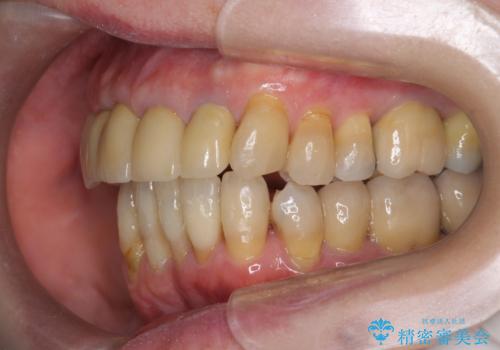

- 上顎前歯の黒ずみの改善、下顎前歯の十度なガタつき、矯正治療とセラミック治療を含む全体的な治療を希望され来院されました。

銀歯を高強度の仮歯に替えたのち、下顎前歯のみの部分矯正→全体的なマウスピース矯正治療(インビザライン)→最終的なセラミック治療と治療を進めます。

矯正治療と目立つ銀歯のやりかえを行ったことでかみあわせだけでなく、審美性・清掃性も改善し口腔内の環境を劇的に改善することができました。